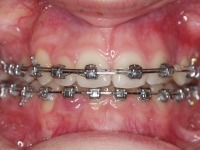

Clase II paciente 15 años

La paciente O.O. acude a nuestra consulta por:

– Canino 13 e incisivo lateral 42 en posición ectópica.

– Canino 23 incluido.

Con lo que decide realizarse un tratamiento de ortodoncia de duración de 24 meses con brackets damon Q.